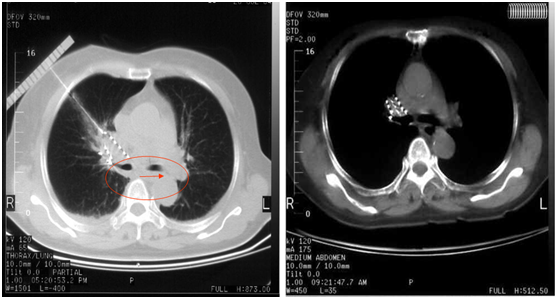

胡教授建议我采用粒子植入联合全身热疗,我对胡教授的治疗方法深信不疑,并且积极配合胡教授的治疗。在半年的治疗过程中,身体慢慢的好起来,感觉自己的精神也好很多。10个月的复查CT看到肿瘤基本没了,只有看到当时做的几个粒子痕迹。

患者李先生治疗前后